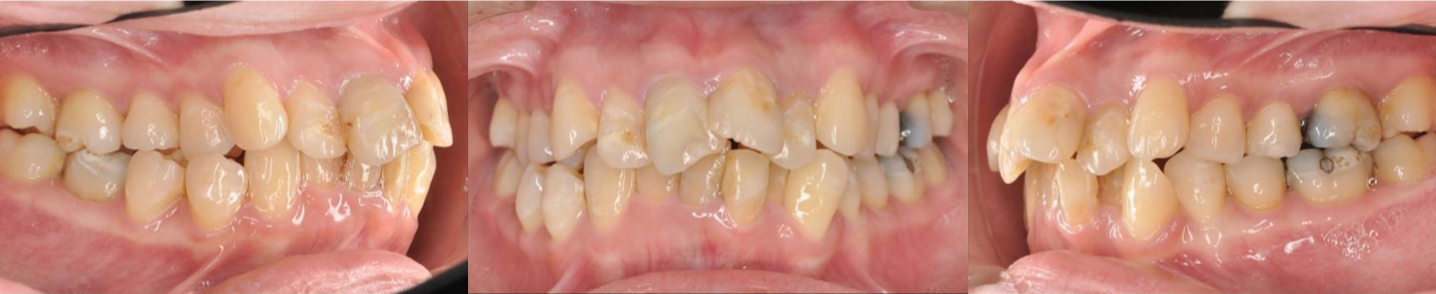

口腔三視圖

治療前